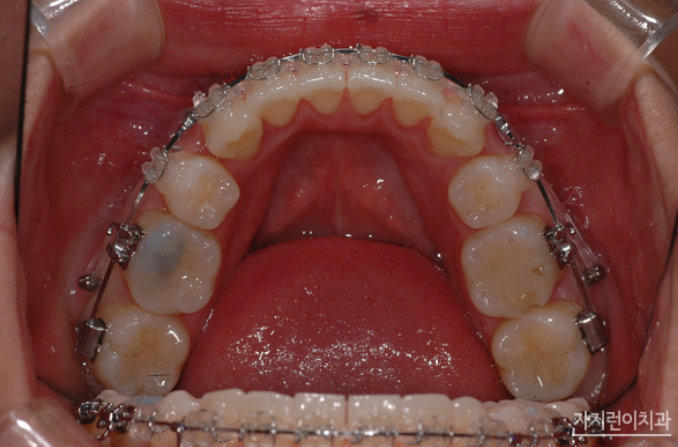

이 사진은 치료가 끝난 후 모습입니다. 다소 흐트러졌던 치열도 가지런하게 배열되었고, 무엇보다 옥니 증상이 확연히 개선된 것을 확인할 수 있었는데요. 도드라져 보이던 상악 돌출도 만족스러울 정도로 개선된 모습을 볼 수 있습니다. 사실 돌출입은 안모 변화가 큰 편이라 살펴보지 않을 수가 없는 부분인데요. 재교정 전에는 상악 돌출로 인해 입이 잘 다물어지지 않았고, 입을 다물기 위해서는 입술 아래 턱에 힘을 주어야만 했다면 이후에는 자연스럽게 입이 다물어지고, 이상적인 측면 페이스라인을 확인해볼 수 있게 되었습니다.